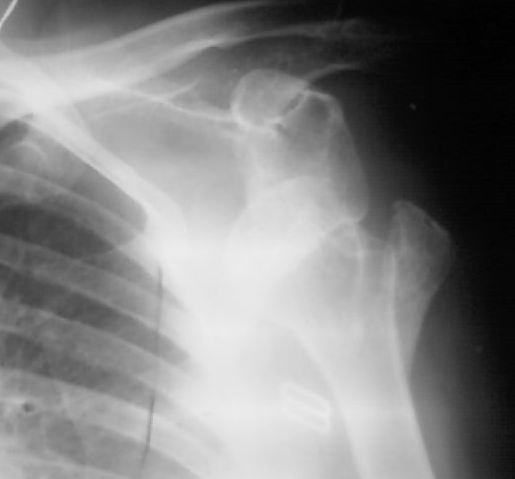

Застарелый вывих плеча

На рентгенснимке левого плеча в передне-задней проекции полный вывих плеча с отрывом большого бугорка. Пальпаторно головка под клювовидным отростком лопатки. Со слов девушки, 6 месяцев назад получила травму, упала на область левого плеча с высоты примерно 2 метров. За медицинской помощью обратилась только сейчас (не знаю почему столько времени находилась без медицинской помощи....почему то пациентка не хочет об этом говорить). Сейчас больше всего беспокоят боли, чем ограничение движений, хотя ограничение движений в левом плечевом суставе существенное.Неврологических и сосудистых нарушений в левой руке нет